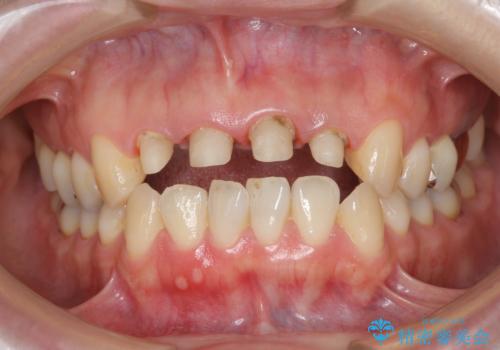

- 歯ぐきの黒っぽさ、暗い色調の前歯の改善を求めて来院されました。

金属を用いたコア・クラウンが装着されており、全ての金属を除去したのちのメタルフリー治療を計画します。